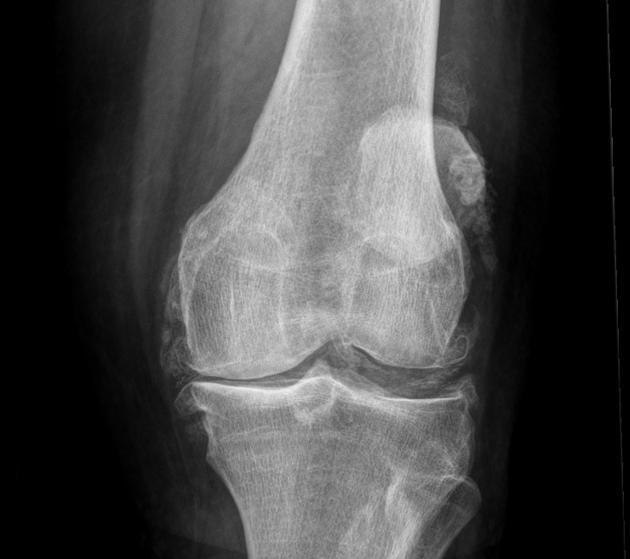

- L'objectif principal de la radiographie est de déterminer si le patient présente un rétrécissement important de l'espace articulaireLa principale raison de ce rétrécissement est que le cartilage s'est considérablement aminci et que l'espace articulaire naturel est plus étroit. En outre, nous pouvons très bien juger les articulations des personnes âgées à l'aide de radiographies.S'il y a une formation osseuse importante (ostéophytes)qui se forment spécifiquement dans telle ou telle partie du corps, les fonctions qu'elles peuvent affecter chez les personnes âgées, et lesLa formation d'ostéoïdes et le rétrécissement de l'espace articulaire sont les changements les plus classiques de l'arthrose.。

- 而L'objectif principal de l'IRM est de déterminer le degré d'usure du cartilage dans les articulations des personnes âgées, la présence de liquide dans les articulations, la quantité de liquide et l'usure du ménisque dans les articulations.Le test est souvent effectué par un médecin. Souvent, les personnes âgées dont les symptômes ne sont pas particulièrement graves et dont les déformations articulaires ne sont pas particulièrement évidentes se prêtent mieux à ce test, mais il va de soi que les personnes qui en ont la possibilité devraient subir les deux tests.

Il est indéniable que la principale cause d'invalidité chez de nombreuses personnes d'âge moyen ou avancé est l'arthrose du genou, qui est à l'origine d'environ 85 % des arthroplasties totales du genou.

Lorsque le cartilage des articulations est usé dans une moindre mesure, le patient ne ressent rien, mais au fur et à mesure que le cartilage s'use de plus en plus sérieusement, l'étendue devient de plus en plus grande, l'épaisseur de l'usure devient de plus en plus grande, alors nos articulations dans le processus de flexion, d'extension et d'activité, la pression entre les os augmente, notre corps afin de mieux réduire la pression sur les articulations entre les os et les os, afin de mieux réduire la pression sur les articulations entre les os, le cartilage est usé de plus en plus gravement, l'épaisseur de l'usure devient de plus en plus grande.trouveront des moyens d'augmenter la taille de l'os, puis des ostéophytes commenceront à apparaître, l'hypertrophie osseuseLa naissance d'une période relativement courte ne produira aucun symptôme, mais si elle est de plus en plus importante, elle affectera de plus en plus la fonction des articulations du patient, ce qui aura pour conséquence que les patients voudront s'accroupir et ne pourront pas descendre, qu'ils voudront plier les jambes et ne pourront pas les plier en position normale, que certains patients apparaîtront également comme de sérieux obstacles au redressement, la situation ci-dessus est très courante chez les personnes âgées, nous l'appelons le "syndrome de l'accroupissement".L'arthrose, dont des études ont montré qu'elle touche 50 % des personnes âgées de plus de 65 ans.。